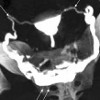

КТ-гистеросальпингография

КТ-гистеросальпингография. Высокотехнологичный метод изучения состояния женской репродуктивной системы, основанный на рентгеновском сканировании матки и придатков с получением поперечных срезов органов. Выполняется после введения рентгеноконтрастного вещества в полость матки. Исследование чаще всего назначается для выяснения причин женского бесплодия, является современной альтернативой рентгеновской ГСГ. Позволяет диагностировать пороки развития матки, внутриматочную патологию, непроходимость маточных труб, новообразования, спаечный процесс в малом тазу. На ценообразование влияет стоимость контраста и расходных материалов.